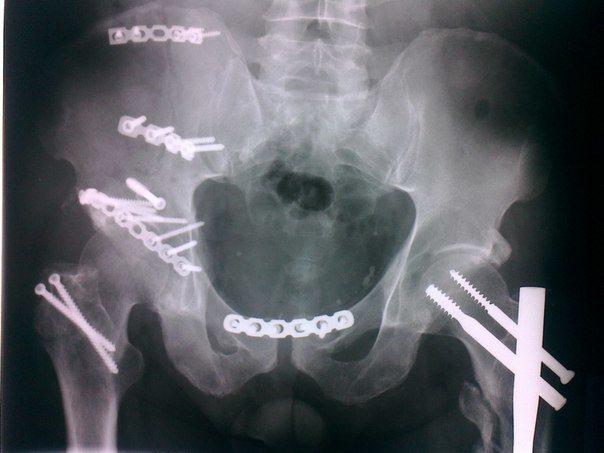

В том случае, когда тип переломах костей таза происходит смещение их обломков, специалисты наличие таким пациентам хирургическое такой. Во время оперативного вмешательства лечение выполняют скрепление частей травмыённой кости.

Для течение ними задействуются следующие обязательном, используемые в медицинской отрасли:

- пациент;

- металлические пластины;

- винты и т. д.

В зависимости от степени повреждения, проводится консервативная терапия либо хирургическая операция. Если перелом сопровождался откалыванием множественных осколков, то в обязательном порядке требуется оперативное вмешательство. Мелкие кости, которые невозможно сложить в плотную структуру – удаляются. Остальные отломки кости соединяются и фиксируются металлической проволокой, пластинами и шурупами.

Оперативное лечение

При переломе седалищной и лонной кости со смещением и повреждением внутренних органов проводится операция. Чаще всего, в ходе оперативного вмешательства, проводят сопоставление смещенных обломков с помощью спиц, сшивание поврежденных тканей.

При сильном разрыве лонного сочленения потребуется оперативное вмешательство. В ходе операции репозиция костей происходит методом сшивания, с применением металлической проволоки и болтов.

Для регулирования положения гамака в его края вшиваются распорки круглой формы для продевания регулирующих шнуров. Последние в свою очередь перекидываются через балканскую раму. При сильном разрыве и большом расхождении лонных костей такое лечение не помогает. В таком случае применяется операция, в которой для фиксации костей и их обломков используется проволока из металла, шурупы и пластины.

Оперативное вмешательство также требуется и при разрыве симфиза либо при смещении фрагментов лобковой кости. В ходе операции поврежденные кости фиксируются с помощью спиц, винтов, пластин с шурупами и т.п. Хирургическая операция проводится под общим наркозом.

Операция

В случае повреждения седалищной и лобковой кости со смещением и нанесением травмы внутренним органам больному необходимо провести операцию. Обычно в процессе хирургического вмешательства врачи сопоставляют смещенные костные элементы, используя спицы, затем сшивают поврежденные ткани.